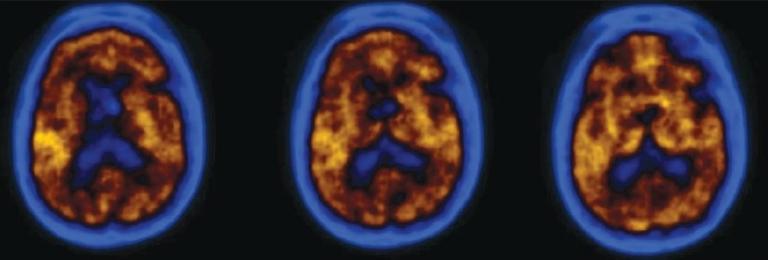

In the patient population included in our study group 36 were normal, 39 had MCI, 40 had AD, 14 had FTD, and 13 had DLBD and 11 dementia due to other miscellaneous causes. MCI patients showed primarily reduced tracer uptake in the mesio-temporal cortex. AD patients showed reduced tracer concentration in temporo-parietal lobes, while patients with advanced diseases showed frontal lobe disease additionally. In subjects of FTD, reduced radiotracer uptake in the fronto-temporal lobes was noted. In addition, FTD patients also showed basal ganglia defects. In contrast the DLBD patients showed globally reduced FDG uptake including severely affecting the occipital cortices.

在我们研究组纳入的患者群体中,36人正常,39人患有MCI,40人患有AD,14人患有FTD,13人患有DLBD,11人因其他各类病因患有痴呆。MCI患者主要表现为内侧颞叶皮质示踪剂摄取减少。AD患者颞顶叶示踪剂浓度降低,而晚期疾病患者还表现出额叶病变。在FTD受试者中,额颞叶放射性示踪剂摄取减少。此外,FTD患者还表现出基底神经节缺陷。相比之下,DLBD患者表现为FDG摄取整体减少,包括严重影响枕叶皮质。